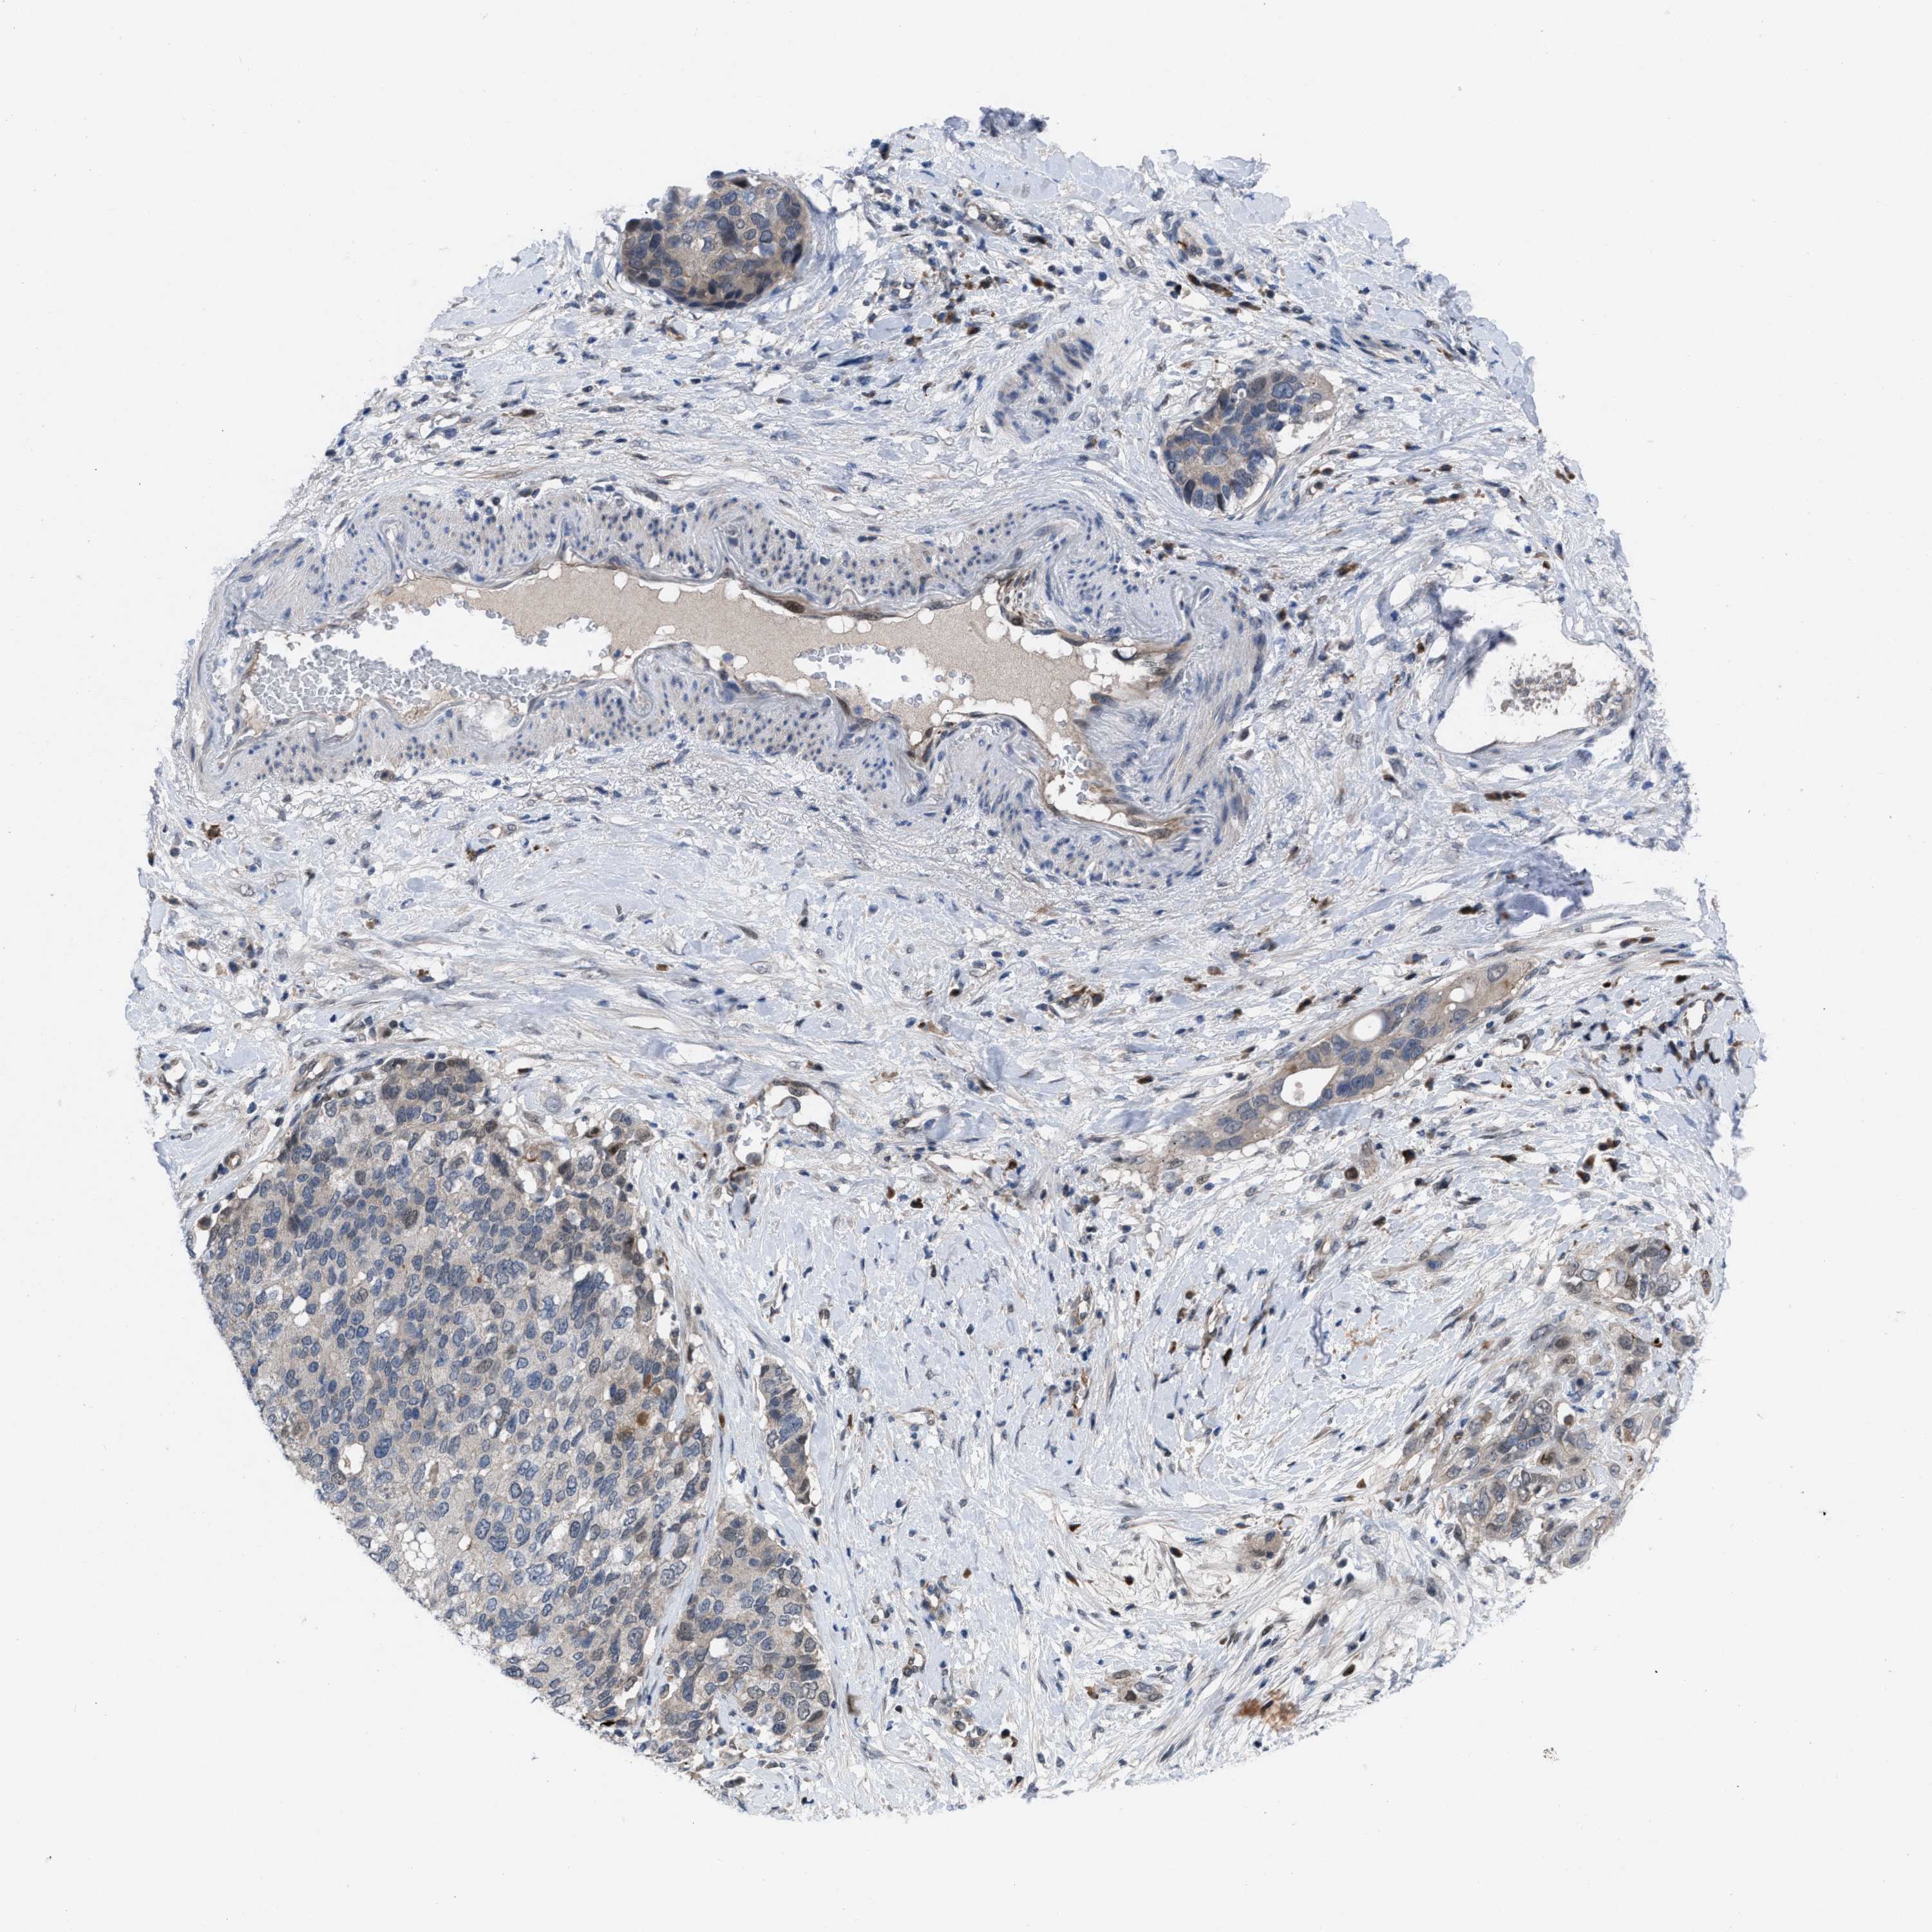

PANCREATIC CANCER - Protein expressioni

A mouse-over function shows sample information and annotation data. Click on an image to view it in a full screen mode. Samples can be filtered based on level of antibody staining by selecting one or several of the following categories: high, medium, low and not detected. The assay and annotation is described here.

Note that samples used for immunohistochemistry by the Human Protein Atlas do not correspond to samples in the TCGA dataset.

Antibody stainingi

Antibody staining in the annotated cell types in the current human tissue is reported as not detected, low, medium, or high, based on conventional immunohistochemistry profiling in selected tissues. This score is based on the combination of the staining intensity and fraction of stained cells.

Each image is clickable and will lead to virtual microscopy that enables deeper exploration of all samples and also displays staining intensity scores, fraction scores and subcellular localization as well as patient and tissue information for each sample.

Antibody HPA019011

Staining

High

Medium

Low

Not detected

Intensity

Strong

Moderate

Weak

Negative

Quantity

>75%

75%-25%

<25%

None

Location

Nuclear

Cytoplasmic/membranous

Cytoplasmic/membranous,nuclear

Adenocarcinoma, NOS